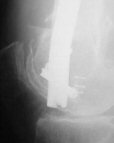

THX, initial images are

1,

2.

At that moment we had in stock only the 10 mm solid nails so of course there was no idea about early weight bearing. But it was quite enough for early knee ROM excersises (see attached). Two locking screws through the distal block provided that.